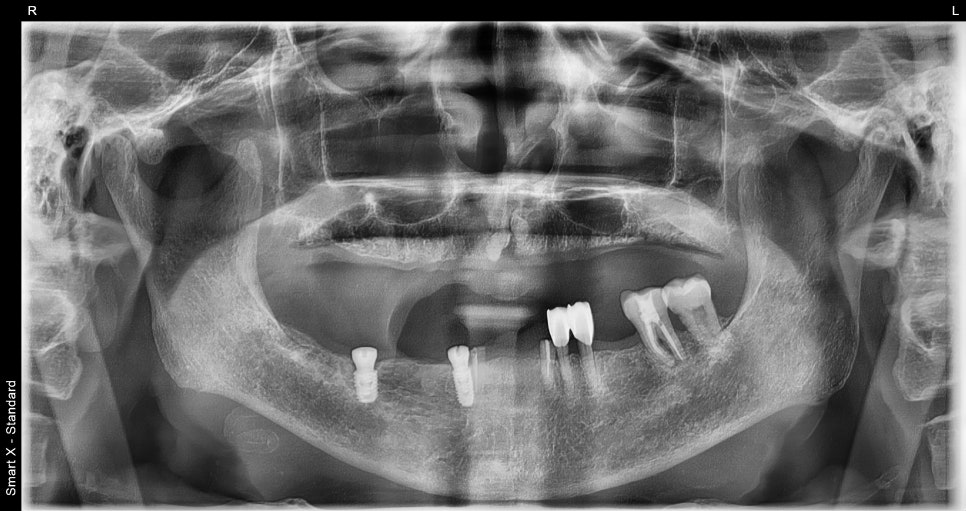

As a result of the diagnosis, the upper jaw required extraction of all remaining natural teeth followed by fabrication of a complete denture.

Although there were still some remaining teeth in the lower jaw,

for stable denture support,

we planned to place two insurance-covered implants

and then fabricate a partial denture.

📌 Before Denture Treatment

– Upper jaw: severe tooth mobility, poor fit of existing denture

– Lower jaw: insufficient partial denture retention, load burden on the gums

After lower jaw insurance-covered implant placement

After full extraction of the upper teeth one month later